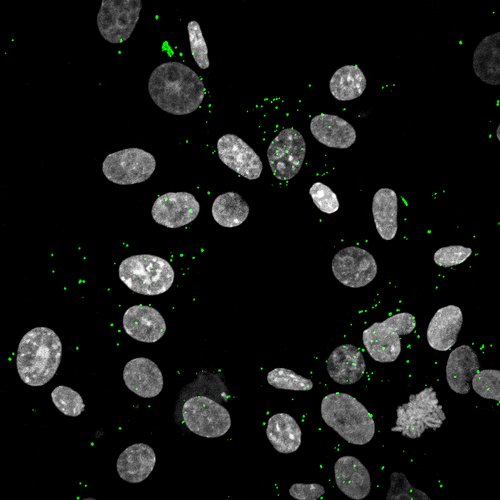

In Laborexperimenten haben die Autoren menschlichen Speichel mit dem jeweiligen Virus (SARS-CoV-2 oder Zika-Virus) zusammengebracht. Anschließend wurden

Zelllinien sowie primäre Mundschleimhautzellen diesen Gemischen ausgesetzt. Um eine Infektion mit dem jeweiligen Erreger nachzuweisen, haben die Wissenschaftlerinnen und Wissenschaftler die Menge der Viren in den Zellen gemessen – mit gegensätzlichen Ergebnissen. Sie fanden nämlich heraus, dass eine Zika-Virus-Infektion bei hoher Speichelkonzentration nahezu ausgeschlossen ist. Für SARS-CoV-2 konnte dieser Effekt nicht nachgewiesen werden.

Die eigentliche Herausforderung bestand jedoch in der Identifikation der Speichelkomponente, die eine Zika-Virus-Übertragung verhindert. Aufgrund ihrer früheren Forschungsergebnisse in Spermaproben lag das besondere Augenmerk der Gruppe auf extrazellulären Vesikeln. „Mithilfe hochspezialisierter Methoden mussten die Vesikel aus dem Speichel aufgereinigt werden. Anschließend konnten wir ihre Zahl, Größe, Identität und antivirale Aktivität bestimmen“, erklärt Dr. Janis Müller, der diese Analysen bei einem Gastaufenthalt am renommierten Karolinska Institut in Stockholm durchgeführt hat.

Insgesamt zeigen die Virologinnen und Virologen, dass das Zika-Virus in der Lage ist, Zellen der Mundschleimhaut zu infizieren. Allerdings wird eine Infektion – ähnlich wie in menschlichem Sperma – durch die körpereigenen extrazellulären Vesikel im Speichel gehemmt. „Die Vesikel sorgen dafür, dass das Zika-Virus nicht an die Zielzelle andocken und diese infizieren kann“, erklären die Erstautoren Carina Conzelmann und Rüdiger Groß. Auf eine Infektion mit dem neuartigen Coronavirus hat dieser Abwehrmechanismus jedoch keinen Einfluss. Demnach scheint die Speichelübertragung beim Zika-Virus keine große Rolle zu spielen, möglicherweise aber bei SARS-CoV-2.